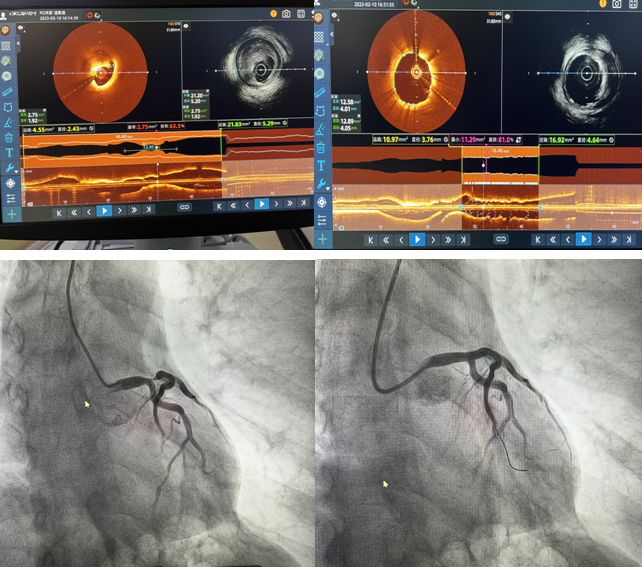

2月10日,我院心內(nèi)二科主任郭明帶領的心臟介入團隊成功完成棗莊市首例IVUS-OCT雙模一體機全程指導PCI手術(shù),標志著我院冠脈介入技術(shù)“精準化”又向前邁進了一大步。

患者,男,71歲,因“發(fā)作性胸痛5天”住院,肌鈣蛋白陽性,胸導聯(lián)T波倒置,臨床診斷為急性冠脈綜合征。冠脈造影檢查示:左前降支開口至左主干重度狹窄達90%,并累及對角支開口狹窄達80%?;颊咦笾鞲杉扒敖抵ч_口同時存在嚴重狹窄,狹窄嚴重且存在不穩(wěn)定斑塊,需更加精準支架定位與覆蓋病變,要保證支架的貼壁絕對良好,此處一旦形成亞急性血栓極有可能引起患者猝死,單純的冠脈影像并不能完全達到此種理想的指導作用。經(jīng)過與患者家屬溝通,郭明主任和楊大成副主任組織團隊人員討論后,決定應用IVUS-OCT雙模一體機全程指導下實施病變血管介入手術(shù)。介入科李紅衛(wèi)主任及盧慶林副主任進行圖像采集及分析解讀,確定冠脈內(nèi)斑塊性質(zhì),精準判定血管直徑、病變長度和支架落腳點,指導選擇合適型號的支架,術(shù)后再次應用IVUS-OCT雙模一體機,觀察支架貼壁及膨脹良好,支架兩端無夾層,手術(shù)取得成功。

近年來如何進行優(yōu)化的介入治療成為當前心血管領域的熱點。單純冠脈造影無論在定性診斷還是定量診斷上,都存在一定的局限性。IVUS具有更深的成像深度,但空間分辨率差;OCT具有更好的分辨率,能更好地對比斑塊成分,但其成像穿透深度有限。因此,單一的IVUS或OCT很難完全提供血管及斑塊內(nèi)部完整的解剖學信息。IVUS-OCT一體機是集光學成像、聲學成像、硬件和軟件于一體的新型血管內(nèi)成像技術(shù),實現(xiàn)了利用一根導管、一次掃描成像就可以完成兩項血管內(nèi)影像檢查,是精準PCI技術(shù)的進一步提升。